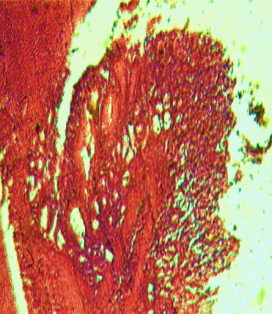

Histological evaluation of gastric lesion

Histological observation showed extensive damage of the gastric mucosa in the ulcer negative control group with necrotic lesions penetrating deeply into the mucosa accompanied by extensive edema and leucocyte infiltration of the submucosal layer (group 2).

Rats that received treatment with aqueous and methanol extracts of the leaves of D. thollonii had comparatively better protection of the gastric mucosa as seen by the reduction of ulcer area, reduced submucosal edema and leucocytes infiltration after 14 days of treatment (fig. 4).

Fig. 4: Histological study of acetic acid-induced gastric damage in rats

In fig. 4: (a’): histological section of a normal control rat: no injuries to the gastric mucosa are seen and the gastric wall is normal. ((b’): histological section of an ulcer negative control rat: there is severe destruction of the surface epithelium and necrotic lesions penetrating deeply into mucosa and submucosa layer. (c’): histological section of rats treated with Maalox (50 mg/kg): the gastric wall appears normally, but there is edema of mucosa and sub mucosa layer.(d’): the histological section of rats treated with Ranitidine (50 mg/kg): the gastric wall appears normally with all layers. (e’): the histological section of rats treated with 125 mg/kg of aqueous extract: there is mild disruption of the sub mucosal layer. (f’): histological section of rats treated with 250 mg/kg aqueous extract: there is moderate disruption of the surface epithelium. (g’): histological section of rats treated with 500 mg/kg of aqueous extract: there is mild disruption of the sub mucosal layer and edema of the muscle. (h’): histological section of rats treated with 125 mg/kg of methanol extracts: there is mild disruption of the epithelium surface and the sub mucosal layer and edema of the serosal layer. (i’): histological section of rats treated with 250 mg/kg of methanol extract: there is mild disruption of the epithelium surface and edema of the submucosal and serosal layers. (j’): histological section of rats treated with 500 mg/kg of methanol extract: there is moderate disruption of the epithelial surface although the gastric wall appears normally.